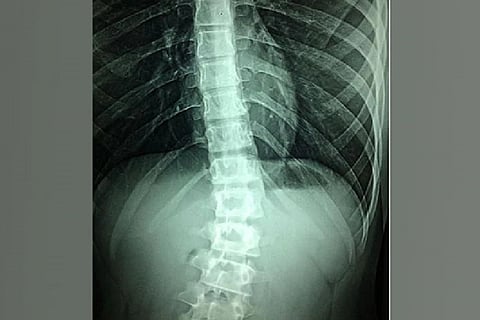

San Diego: According to a new study, chronic pain spinal cord stimulation (SCS) uses an implanted device to supply a small amount of electricity directly to the spinal cord, altering or blocking nerve activity and minimizing the sensation of pain reaching the brain. The findings of the research were published in the journal 'Bioelectronic Medicine', a research team led by scientists at the University of California San Diego School of Medicine.

Scientists reported high-frequency SCS proved more effective at improving perceived pain reduction (PPR) than low-frequency SCS in patients studied, and there was some variation in PPR between male and female patients. Low-frequency SCS (50 Hz) was originally approved by the U.S. Food and Drug Administration (FDA) as a treatment for intractable back and leg pain in 1989. In 2015, the FDA approved high-frequency SCS (10,000 Hz), which delivers electrical stimulation pulses that are shorter in duration, lower in amplitude and do not induce paresthesia, the abnormal sensation of tingling or prickling.